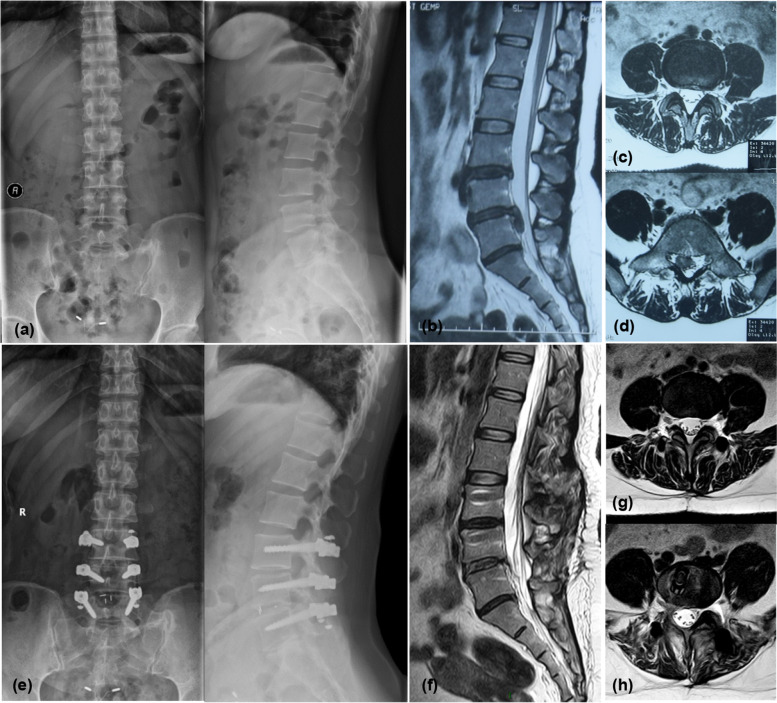

Fig. 2.

Typical case. The patient was a 40-year-old woman who was diagnosed with lumbar disc herniation (L4/5), cauda equina syndrome, and L3/4 disc degeneration and underwent L3-5 hybrid surgery with PEEK rods. a shows the lumbar X-ray before the operation. b shows the sagittal-plane MRI image of the lumbar region before the operation.c, d show the MRI images of the L3/4 and L4/5 sections of the lumbar region before the operation, respectively. e shows the lumbar X-ray at the 2-year follow-up. f shows the sagittal MRI image of the lumbar region at the 2-year follow-up. g, h show the MRI images of the L3/4 and L4/5 sections of the lumbar region at the 2-year follow-up, respectively. L3-5 were fixed segments, L3/4 was nonfused segments, the modified Pfirrmann classification of L3/4 was 6 both pre- and postoperatively, and the DHI was 0.28 preoperatively and 0.26 postoperatively. The modified Pfirrmann classification of the upper adjacent segment L2/3 was 2 both pre- and postoperatively, and the DHI was 0.33 preoperatively and 0.35 postoperatively. No significant degeneration was seen